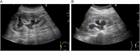

1. 片側の腰背部痛や側腹部痛では水腎症を念頭に置き、まず超音波検査を行い、尿路閉塞の位置と原因を同定するには単純CTを撮影する。